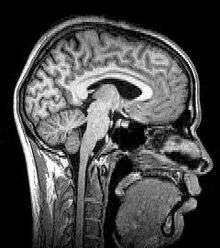

Magnetic resonance imaging (MRI) uses magnetic fields and radio waves to produce high quality two- or three-dimensional images of brain structures without use of ionizing radiation (X-rays) or radioactive tracers.